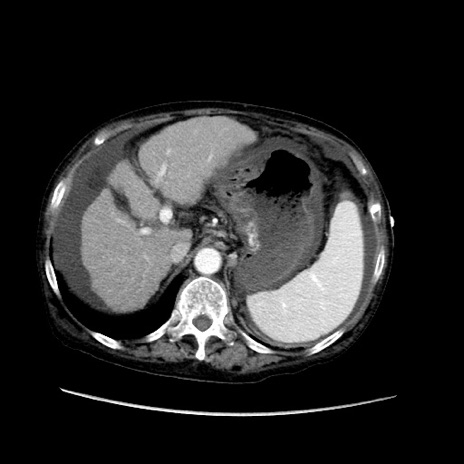

冠状断像

【症例】80歳代 女性

【主訴】腹部膨満感

【現病歴】他院にて肝硬変にてフォロー中。1週間前から便秘、腹部膨満感、臍部腫瘤あり受診となる。

【既往歴】肝硬変

【身体所見】腹部膨隆あり、皮膚変化なし、疼痛なし。

【データ】WBC 4600、CRP 0.25